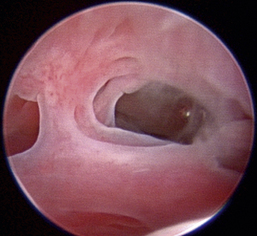

Normal turbinates have a smooth, pink-to-white surface and a spatial alignment that provides channels for the passage of air. The color varies and appears tan in the caudal nasal cavity. Turbinates come in different shapes and sizes, but the surface should be smooth. Ethmoid turbinates in the caudal nasal cavity will have a characteristic stippled or corrugated appearance (Figures 19-13 through 19-16). Ulcerations or various proliferations of the mucosa are indicative of disease. These changes are typically diffuse and accompanied by a lot of mucus. Mucus can be thin to purulent. Copious amounts can be flushed out of the nasal cavity to allow better visibility. The specific disease is determined by biopsy. After full examination of the nasal cavity, run the scope along the floor of the nasal sinus to the level of the choanae. Keeping the scope pointed in a ventral medial direction prevents inadvertent trauma or penetration of the cribriform plate. The index finger of the free hand can be used to follow the scope as it moves caudally over the hard palate; the surgeon can then palpate the scope through the soft palate when it moves into the nasopharynx. Some force is needed to complete this procedure and may result in increased bleeding.

image

Figure 19-15 Normal canine nasal turbinate mucosa.